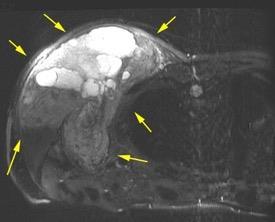

50% de los tumores de partes blandas.

Predilección varones en lipomas profundos

30% “hereditarios”

Isointenso con grasa subcutánea

Burt AM et al. Imaging review of lipomatous musculoskeletal lesions. SICOT J2017/ Murphey MD et al. From the archives of the AFIP: benign musculoskeletal lipomatous lesions. Radiographics. 2004